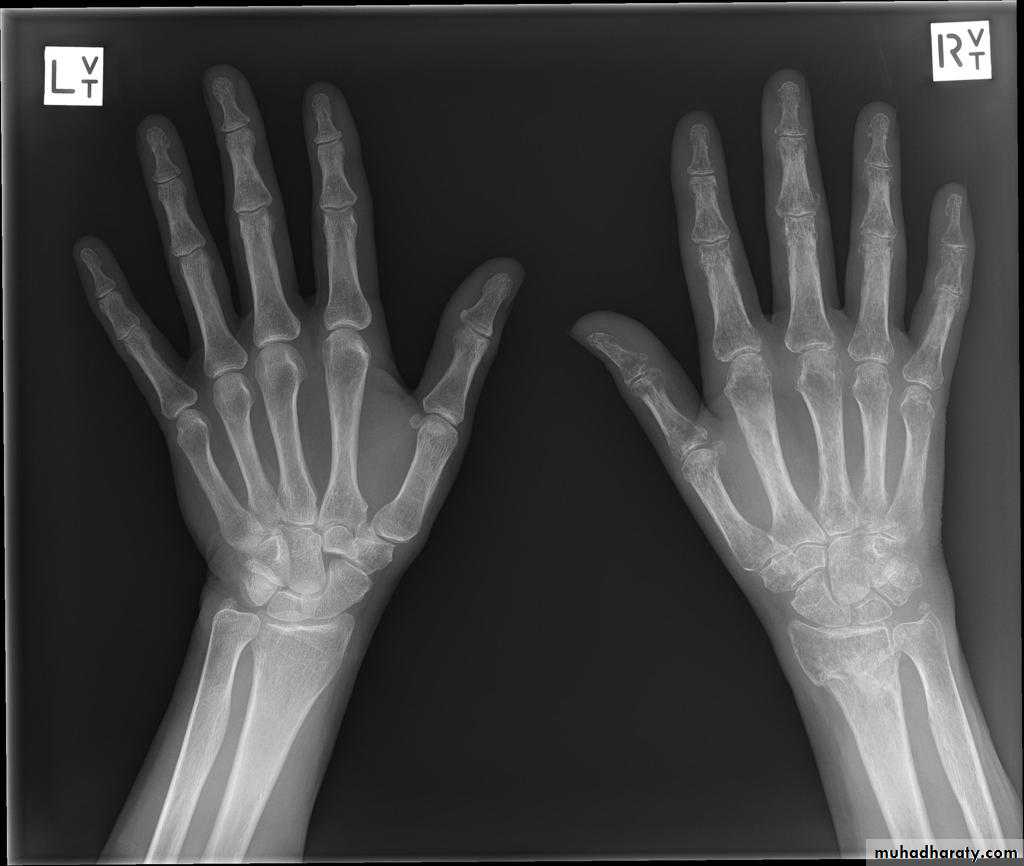

Sudeck’s atrophy :

Algodystrophy , reflex sympathetic dystrophy , complex pain regional syndrome ( all refer to same entity )C.F. : continuous ‘ burning ‘ pain. local swelling, redness and warmth, and tenderness.

After few weeks the skin becomes pale and atrophic, movements are increasingly restricted.

X-rays characteristically show patchy rarefaction of the bone.

Treatment :

Elevation and active exercises are essential to prevent and to treat CRPS.- antiinflammatory drugs and adequate analgesia are helpful.

- use of drugs like amitriptyline, carbamazepine , gabapentin and calcium channel blockers may help.